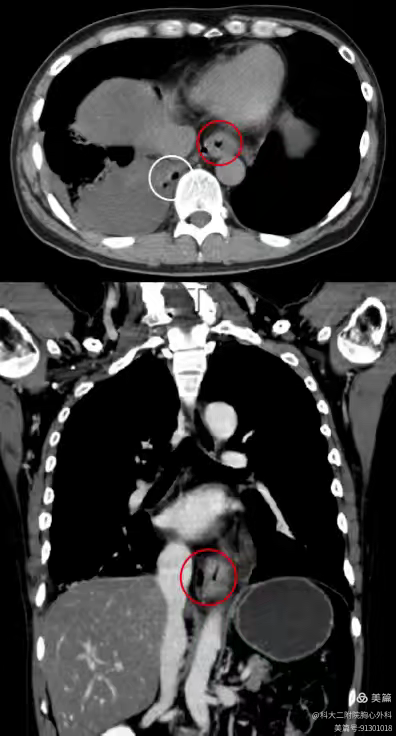

前不久的一次聚餐中,李叔叔在饮用鱼汤后突发剧烈呕吐,右背部出现强烈的疼痛感。李叔叔被紧急送往河南科技大学第二附属医院胸心外科就诊,胸部 X 光片捕捉到了胸腔积液的异常阴影,随后的 CT 检查更清晰地揭示了危机源头——食管壁异常增厚、周围气体影密布,消化道造影显示有穿孔,李叔叔最终被确诊为 食管破裂。